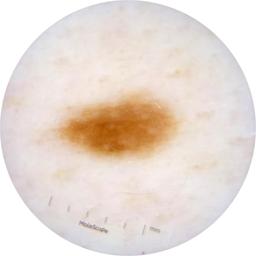

ISIC_9751750

2009 x 2009

acquisition_day 410

age_approx 50

anatom_site_1 Trunk

anatom_site_2 Posterior trunk

anatom_site_general posterior torso

diagnosis_1 Benign

diagnosis_confirm_type single image expert consensus

image_type dermoscopic